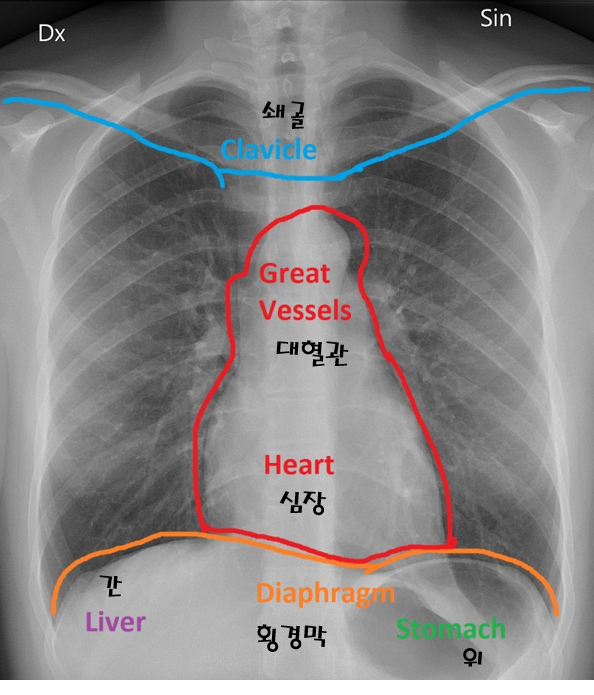

- 폐렴이 의심되는 환자를 촬영할 땐, image Receptor를 가슴 쪽에 두고 사진을 찍게 되죠. 보통 이러한 사진을 Chest-Xray라고 합니다.

- 본래 폐포는 공기(기체) 상태인데, 폐렴으로 인해 액체가 폐포에 가득해지면 X-ray 촬영 시, 아래와 같이 X-ray 이미지가 나오게 됩니다. (왼쪽 이미지: 정상(normal), 오른쪽 이미지: 폐렴(pneumonia))

[Q. X-ray 이미지에서 AP, PA는 무엇을 의미하나요?]

Chest X-ray (CXR)를 찍을 때 찍는 방향에 따라 AP(Anterior-Posterior)와 PA(Posterior-Anterior)로 나눌 수 있습니다.

Chest X-ray의 경우 찍는 방향에 따라 나오는 X-ray 이미지 상태가 다릅니다.

보통, AP 방식으로 찍기보다 PA 방식을 찍는데 그 이유는 아래와 같습니다.

- AP view: 심장이 확대되어 보이며, 견갑골에 의해 폐야가 많이 가려지며, 횡경(Diaphragm)막이 높이 올라가 있어 폐가 좁게 나타남